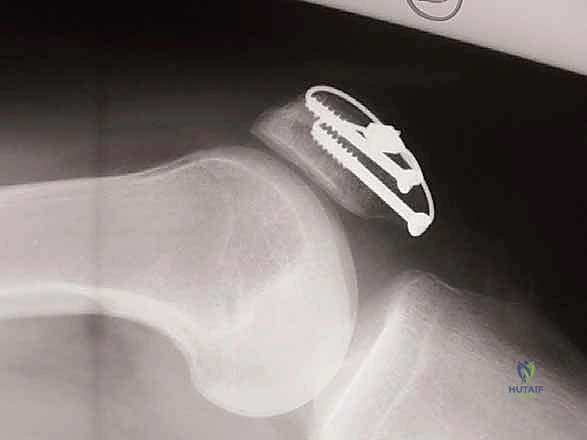

الدليل الشامل لعملية التثبيت الداخلي بالأسلاك (ORIF with Tension Band Wiring) خطوة بخطوة

تُعتبر تقنية "شريط التوتر" (Tension Band Wiring - TBW) المعيار الذهبي والأكثر استخدامًا في علاج كسور الرضفة المستعرضة. تعتمد هذه التقنية الميكانيكية العبقرية على تحويل قوى الشد (Tensile forces) التي تولدها العضلة الرباعية في الجزء الأمامي من الرضفة، إلى قوى ضغط (Compressive forces) تفيد في التئام الكسر في الجزء الخلفي (المفصلي).

إليكم تفصيل دقيق لخطوات العملية كما يجريها الخبير الأستاذ الدكتور محمد هطيف، مع التركيز على الدقة الجراحية والأمانة الطبية: